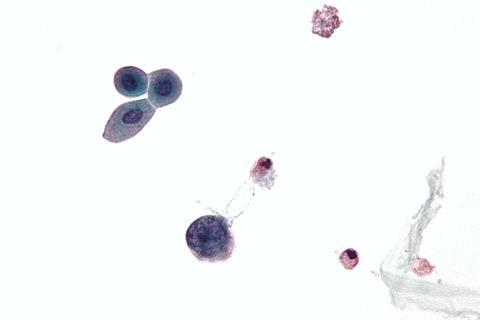

In laboratory studies using the human tissue that lines the urinary tract (urothelium), the team observed DNA damage patterns caused by the cell’s antiviral defences after controlled exposure to BK virus - the childhood infection identified earlier as lying dormant in the kidney.

In this fight against BK virus “friendly fire” from enzymes meant to damage the virus can cause collateral damage in the cells’ own DNA. This evidence supports a theory in which an individual’s own antiviral response to BK virus infection causes the DNA mutations that can lead to cancer.

“We found that DNA damage happens not only in infected cells but also in surrounding ‘bystander cells’, witnessing infection in their neighbours. This is important because it might explain why most bladder cancers have no sign of the virus in them when they are diagnosed many years later.”